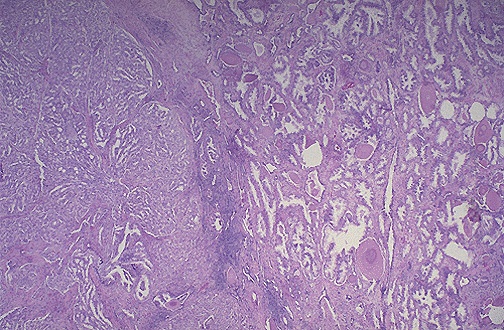

| At the right are normal prostatic glands containing scattered corpora amylacea. At the left is prostatic adenocarcinoma. Note how the glands of the carcinoma are small and crowded. Prostatic adenocarcinomas are given a histologic grade (Gleason's grading system is used most often, and includes a score of 1 to 5 for the most prominent component added to a score of 1 to 5 for the next most common pattern). For example, this adenocarcinoma could be given a Gleason grade of 3/3. |